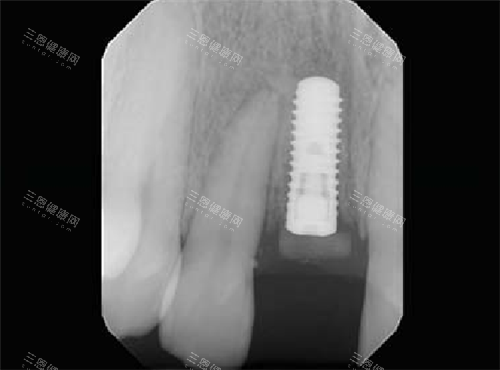

医生好靠谱,佢会细心听我讲自己牙齿嘅问题,仲用啲特色嘅仪器帮我做咗多方面嘅检查。经过检查,医生认为我适合做种植牙,仲详细哋跟我讲解咗种植牙嘅过程、优缺点以及需要注意嘅事项。

整个过程都好娴熟,虽然我心里都有啲紧张,但系医生同护士嘅鼓励同安抚,令我慢慢放松咗。而且技术方面真系冇得弹,医生嘅手法好熟练,每一步都做得比较准。

经过一段时间嘅治疗,我嘅种植牙改善真系好理想,外观同真牙冇咁大分别,而且用起身都好方便,冇任何唔舒服嘅感觉。